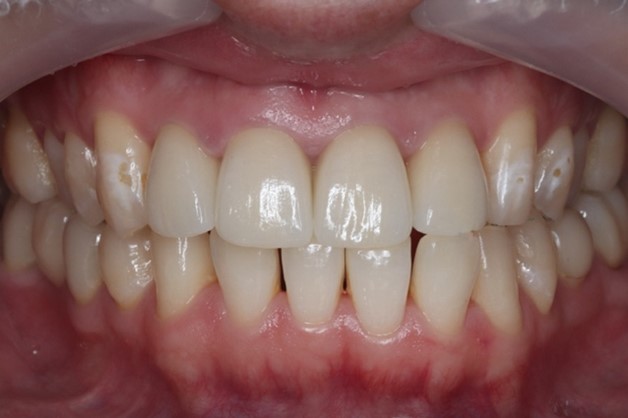

かみ合わせの調和と、周りの天然歯と馴染む色の仕上がりにすることで、審美的回復を機能面と見た目を両立して実現しました。

歯肉の状態は非常に健康な状態に保たれ、かみ合わせも仮歯製作時と同様に良好です。

今回の患者様は歯と歯茎の境目と、前歯部の色を気にされていました。前歯の詰め物をオールセラミックの材料でやり変えることで、自然で明るい口元を実現しています。